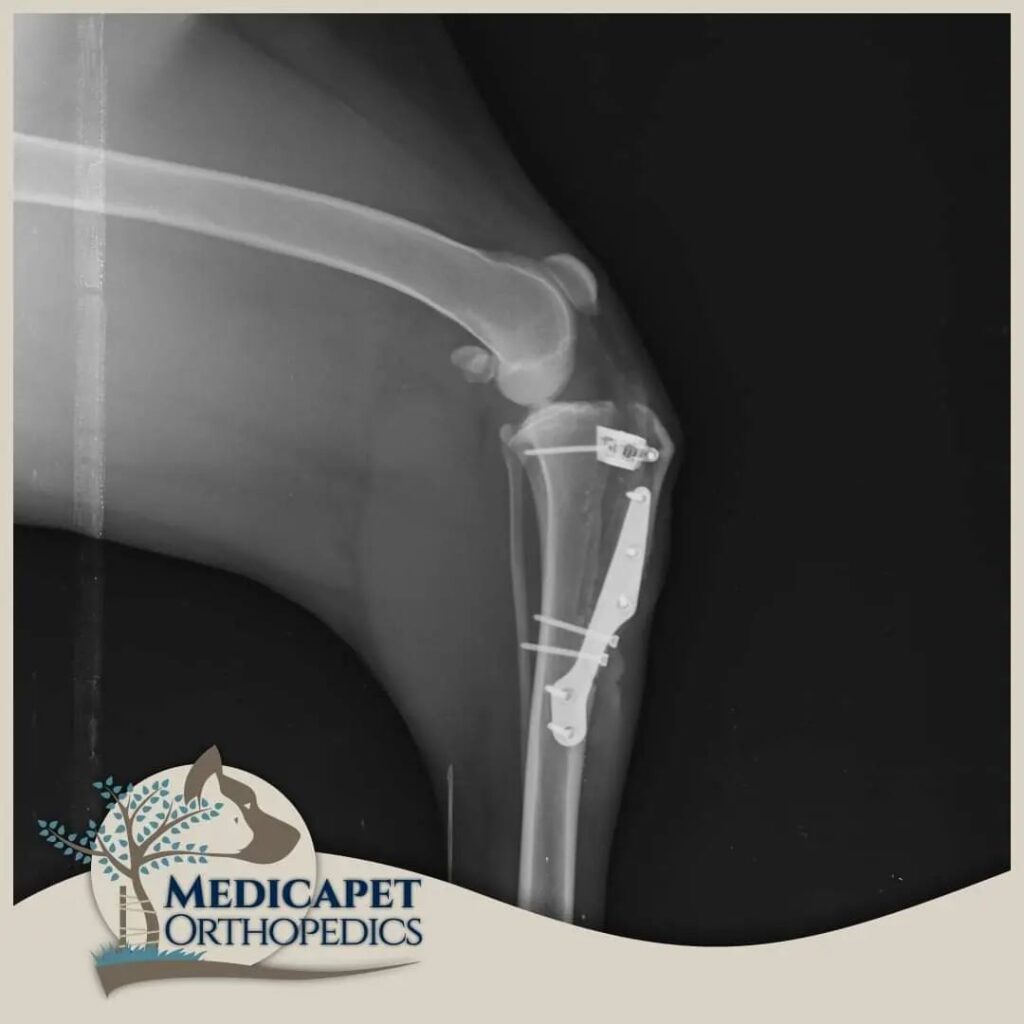

TPLO – Tibial plato seviyeleme osteotomisi

Bu ameliyat, tibianın üst kısmında dairesel bir kesi oluşturulmasını ve kemikteki önceki eğim artık mevcut olmayana kadar plato segmentinin döndürülmesini içerir. Daha sonra kemik, kemik plakası ve vidalar kullanılarak bu yeni pozisyonda sabitlenir. Böylece femurun tibia üzerinde uygunsuz şekilde kayması engellenmiş olur. Hassas ölçümler ve kusursuz el maniplasyonu gerektirdiği için tecrübeli ve ehil cerrahlar tarafından uygulanmalıdır.